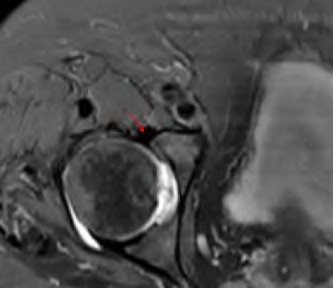

A 75-year-old man underwent total hip arthroplasty 10 years ago. He now reports mild groin pain which has been increasing lately. What is the most likely explanation for the finding in Figure A indicated with the arrows?

Osteolysis of the pelvis is a common complication associated with total hip arthroplasty. Osteolysis affects sockets with and without cement, and has been attributed to the biologic reaction to wear debris. With well-fixed cementless sockets, an expansile pattern of osteolysis is usually seen.

The radiographic appearance has a radiolucent area that starts at the implant-bone interface and expands into the cancellous bone away from the implant.

This pattern of osteolysis can be explained with the concept of effective joint space. This concept states that joint fluid and wear particles will flow according to pressure gradients and follow the path of least resistance.

The Level 5 review article by Chiang discusses osteolysis in further depth.